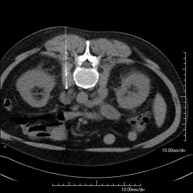

Prova diagnòstica que consisteix en l'estudi de l'abdomen d'alta definició anatòmica (fetge, vesícula biliar, via biliar, pàncrees, melsa, estómac, intestins, ronyons, estructures vasculars, bufeta, úter i ovaris, etc.) mitjançant l'ús d'un equip de TC (Tomografia Computeritzada). Aquestes imatges s'estudien posteriorment en una estació de treball que permet obtenir reconstruccions bidimensionals en diferents plànols de l'espai i també reconstruccions 3D (volumètriques). La majoria d'estudis requereixen l'ús de contrast iodat per millorar la definició de les imatges. - TC Pelvis

Prova diagnòstica que consisteix en obtenir imatges bi i tridimensionals de l'abdomen d'alta definició anatòmica (estructures òssies, estructures vasculars, fetge, pàncrees, vesícula biliar, ronyons, glàndules suprarenals, melsa, intestí prim i gros, bufeta, úter i ovaris, pròstata i vesícules seminals, urèters, etc.) mitjançant l'ús d'un equip de TC (Tomografia Computeritzada). La majoria d'estudis requereixen l'ús de contrast iodat. - TC Fetge